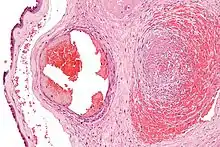

Excessive generation of fibrin due to activation of the coagulation cascade leads to thrombosis, the blockage of a vessel by an agglutination of red blood cells, platelets, polymerized fibrin and other components. Ineffective generation or premature lysis of fibrin increases the likelihood of a hemorrhage.

Fibrin is formed after thrombin cleavage of fibrinopeptide A (FPA) from fibrinogen Aalpha-chains, thus initiating fibrin polymerization. Double-stranded fibrils form through end-to-middle domain (D:E) associations, and concomitant lateral fibril associations and branching create a clot network.[5][6] Fibrin assembly facilitates intermolecular antiparallel C-terminal alignment of gamma-chain pairs, which are then covalently 'cross-linked' by factor XIII ('plasma protransglutaminase') or XIIIa to form 'gamma-dimers'. The image at the left is a crystal structure of the double-d fragment from human fibrin with two bound ligands. The experimental method used to obtain the image was X-ray diffraction, and it has a resolution of 2.30 Å. The structure is mainly made up of single alpha helices shown in red and beta sheets shown in yellow. The two blue structures are the bound ligands. The chemical structures of the ligands are Ca2+ ion, alpha-D-mannose (C6H12O6), and D-glucosamine (C6H13NO5).[7]